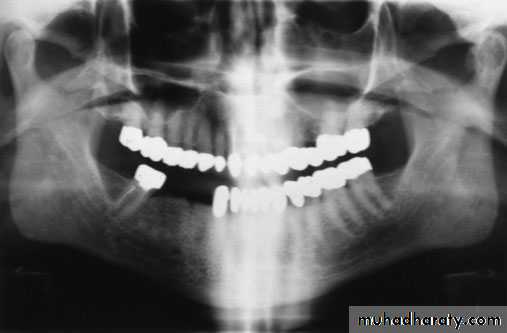

radiographic examination

• Transcranial view

• Transpharngyal view

• Panoramic view

• *CT *MRI *EMG * cone beam tomography *Cast sometime needed to analyze the occlusion